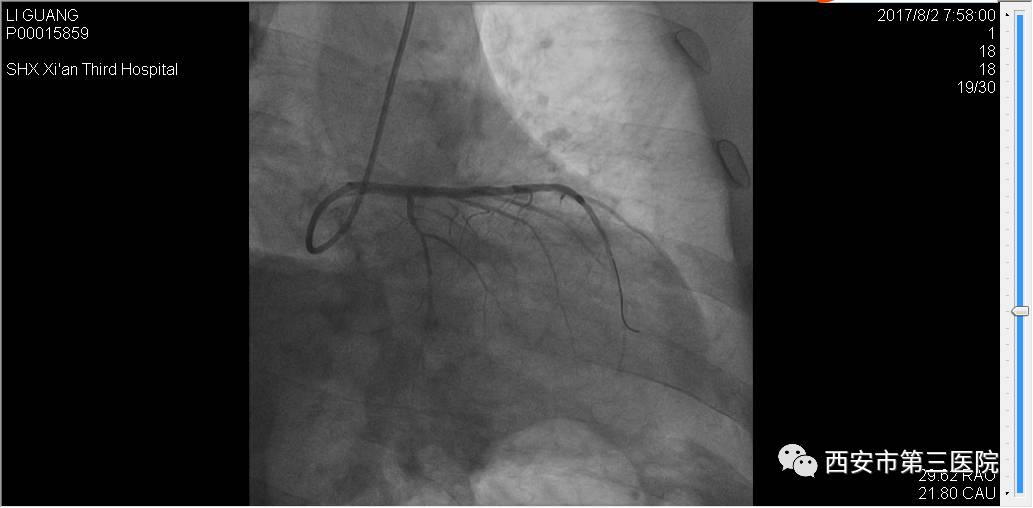

手术后